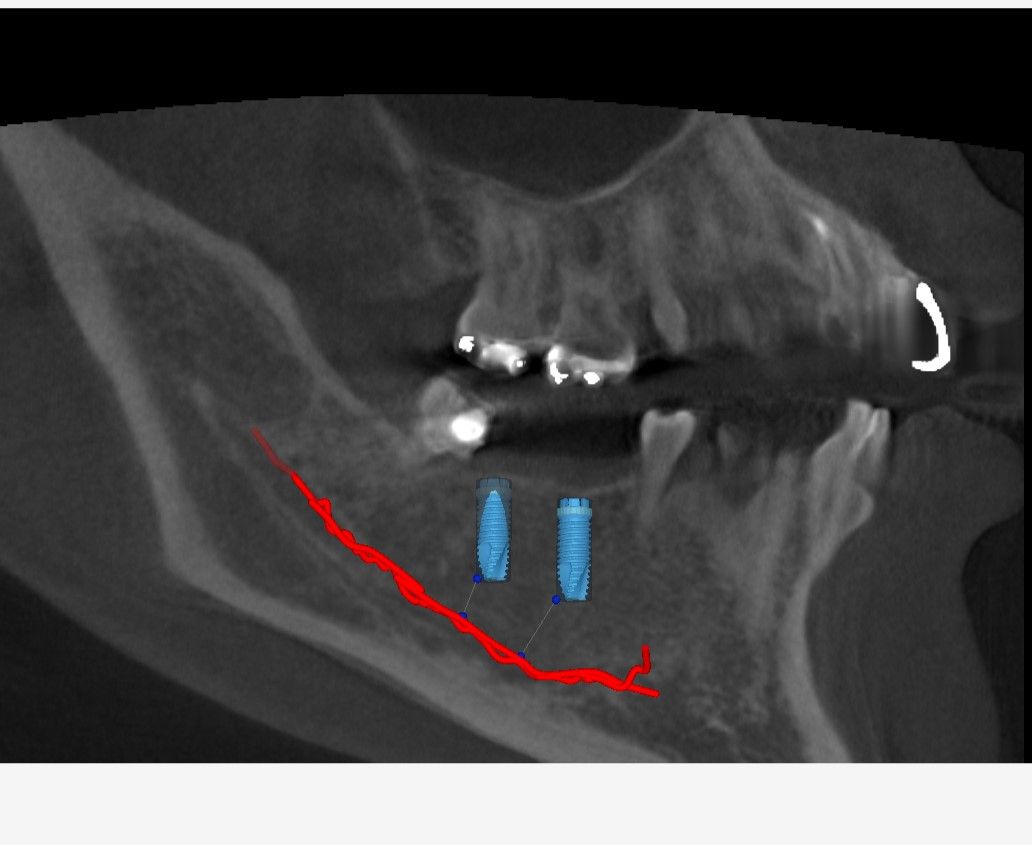

先日インプラントの型取をした患者さんの被せ物が出来上がってきました。

これをネジを使ってインプラントに接続します。